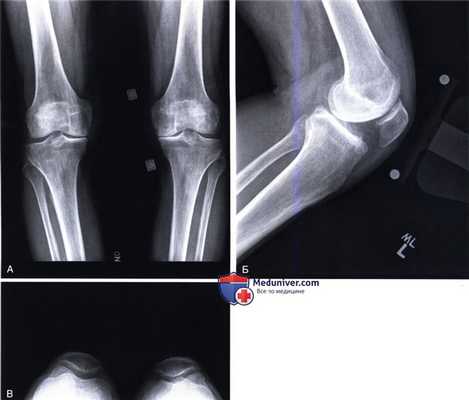

б) Рентгенологическое обследование включает рентгенограммы стоя в прямой проекции, в боковой и аксиальной проекциях (рис. 1):

• Рентгенограммы позволяют оценить выраженность дегенеративных изменений, ось коленного сустава, качество и дефицит костной ткани

в) Для более точного предоперационного планирования необходима рентгенография конечности целиком с захватом тазобедренного, коленного и голеностопного суставов (рис. 2)

• Механическая ось конечности определяется построением прямой линии, соединяющей центр головки бедренной кости через центр коленного сустава с центром голеностопного сустава

г) Стресс-рентгенография в прямой проекции позволяет оценить целостность коллатеральных связок и возможность пассивной коррекции варусной деформации

д) Полезным при предоперационном планировании будет предварительное определение размеров компонентов и глубины опилов с помощью шаблонов (рис. 3):

• Высота проксимального большеберцового опила

• Необходимость дополнительной аугментации медиального плато по выполнении опила

• Высота дистального опила бедра

• Возможные размеры имплантов.